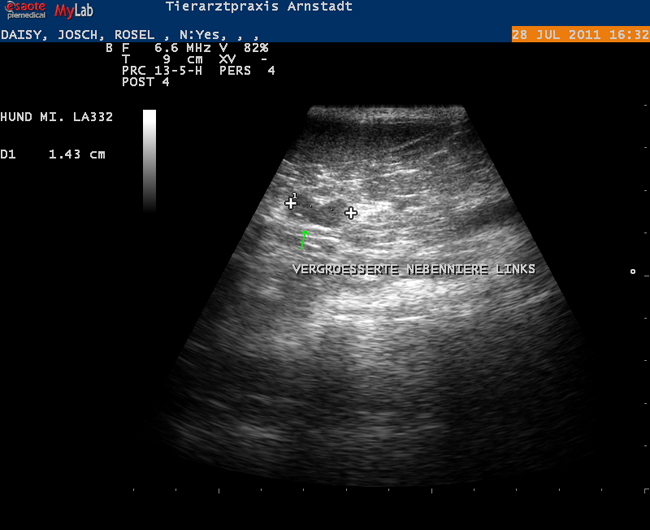

Die Untersuchungstechnik mittels Ultraschall ist insbesondere im Weichteilgewebe geeignet, Befunde zu erheben.

Wir führen in unserer Praxsis abdominale sowie kardiologische Ultraschalluntersuchungen durch.

Beispiele: